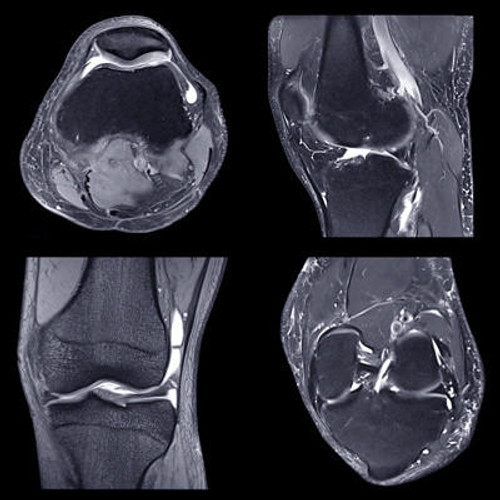

Comprehensive updates cover all subspecialties, from neurologic and musculoskeletal, to cardiac and breast imaging. Plus, pediatric, emergency, PET/CT, oncologic, and interventional topics with emphasis on safety, quality, and AI use.